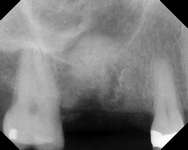

Figure 1A through Figure 1C Buccal and radiographic views of posterior edentulism with significant sinus pneumatization in the molar region.

Figure 1D Lateral wall osteotomy.

Figure 1E The osteotomy was grafted with particulate bone. Figure 1F The surgical site was covered with a resorbable barrier.

Figure 1G Radiographic confirmation of bone regeneration 8 months after surgery. Figure 1H Radiographic confirmation of implant osteointegration into the new bone 14 months after the initial surgery. Figure 1I. Final implant-supported restoration.